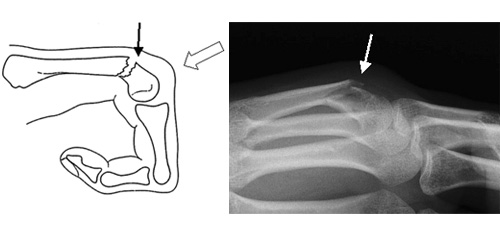

医師があなたの怪我を診断します。評価の一環として、怪我がどのように起こったかを尋ねられます。骨が折れているかどうか、および第 5 中手骨の首が折れているかどうかを判断するには、 X 線検査が必要になる可能性が高くなります。医師は、別の骨が折れていないか、別の場所にあるのかを確認する必要があります。骨折の種類によって治療法が異なるため、診断には特に注意が必要です。